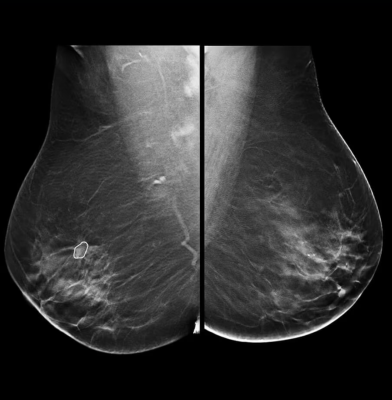

GE HealthCare’s latest MyBreastAI Suite provides an all-in-one AI platform optimized for mammography to support clinicians with breast cancer detection. With this initial release, MyBreastAI Suite integrates three AI applications from iCAD including ProFound AI for DBT, SecondLook for 2D Mammography and PowerLook Density Assessment to help support early detection and improve patient outcomes, as well as help radiology departments improve operational productivity.

With Pristina Bright, clinicians can see lesions that cannot be seen on routine mammography4 5 6 and biopsy what is seen within 15 minutes.7 To help improve overall productivity, Pristina Bright can also help providers take more patients on their system, with the ability to image up to 30 patients a day with contrast mammography8 through an easy-to-read exam.

“Through our research and clinical experiences, contrast enhanced mammography (CEM) continues to emerge as game-changer in helping to improve breast cancer outcomes for patients facing this difficult diagnosis,” shares Dr. Jordana Phillips – Radiologist at Boston Medical Center. “When it comes to findings that are difficult to define, CEM leverages the addition of a contrast agent to highlight unusual areas of blood flow - providing an efficient yet familiar, patient-centric approach to evaluate the presence of cancer with high sensitivity and specificity. With contrast, we’re able to turn a normal mammogram into something that provides so much more information which accelerates our ability to make a confident diagnosis. We’re excited to be joining GE HealthCare and the breast imaging community at SBI 2024 to share more about our experience through the hands-on learning course, as well as share how we’ve implemented CEM as part of our efforts to provide personalized breast cancer care to community we serve.”

- SenoBright HD Contrast Enhanced Mammography (CEM), which combines mammography and vascular-based screening methods to highlight areas of unusual blood-flow patterns that may indicate malignancy - helping reduce the masking effect of fibro glandular breast tissue so lesions can be more clearly identifiable; and